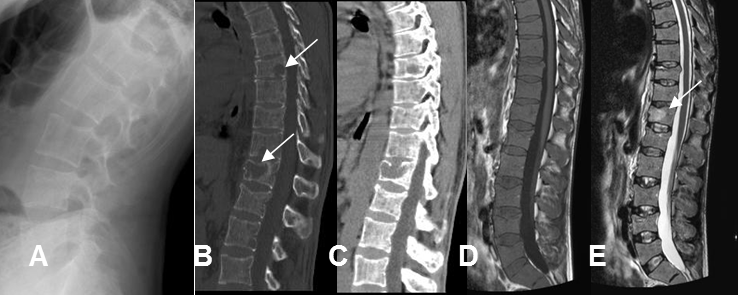

Fig 12 B. Mieloma.

A: Rx lateral. Presencia de osteopenia generalizada.

B: TAC reconstrucción lateral en ventana de hueso y C: TAC reconstrucción sagital en ventana de tejido. Se confirma la osteopenia y adicionalmente hay otras lesiones líticas, en los cuerpos dorsolumbares.

D: RM sagital en T1 y E: RM sagital en T2. Medula osea hipointensa en T1, por reemplazo y lesión lítica, hiperintensa en T2, sobre el cuerpo de D12. Estos cambios corresponden a mieloma múltiple.